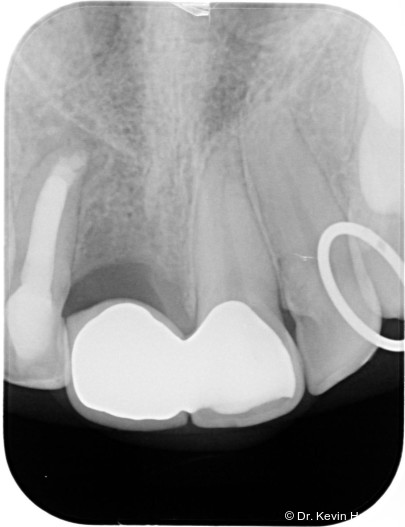

Klinisch zeigten sich die Zähne 12 und 13 karies- und füllungsfrei. Zahn 12 reagierte nicht auf Sensibilitätstests und war leicht perkussionsempfindlich. Zahn 13 reagierte unauffällig. Radiologisch zeigte sich eine ausgedehnte apikale Aufhellung am Zahn 12 sowie eine Hartgewebsformation im apikalen Kanallumen (Abb. 1–2d).

Geplant wurde eine Wurzelkanalbehandlung an Zahn 12. Die zunächst vorgesehene Zystektomie mit Wurzelspitzenresektion wurde zurückgestellt, um die Heilungstendenz nach orthograder Therapie zu beurteilen und einen chirurgischen Eingriff möglichst zu vermeiden.